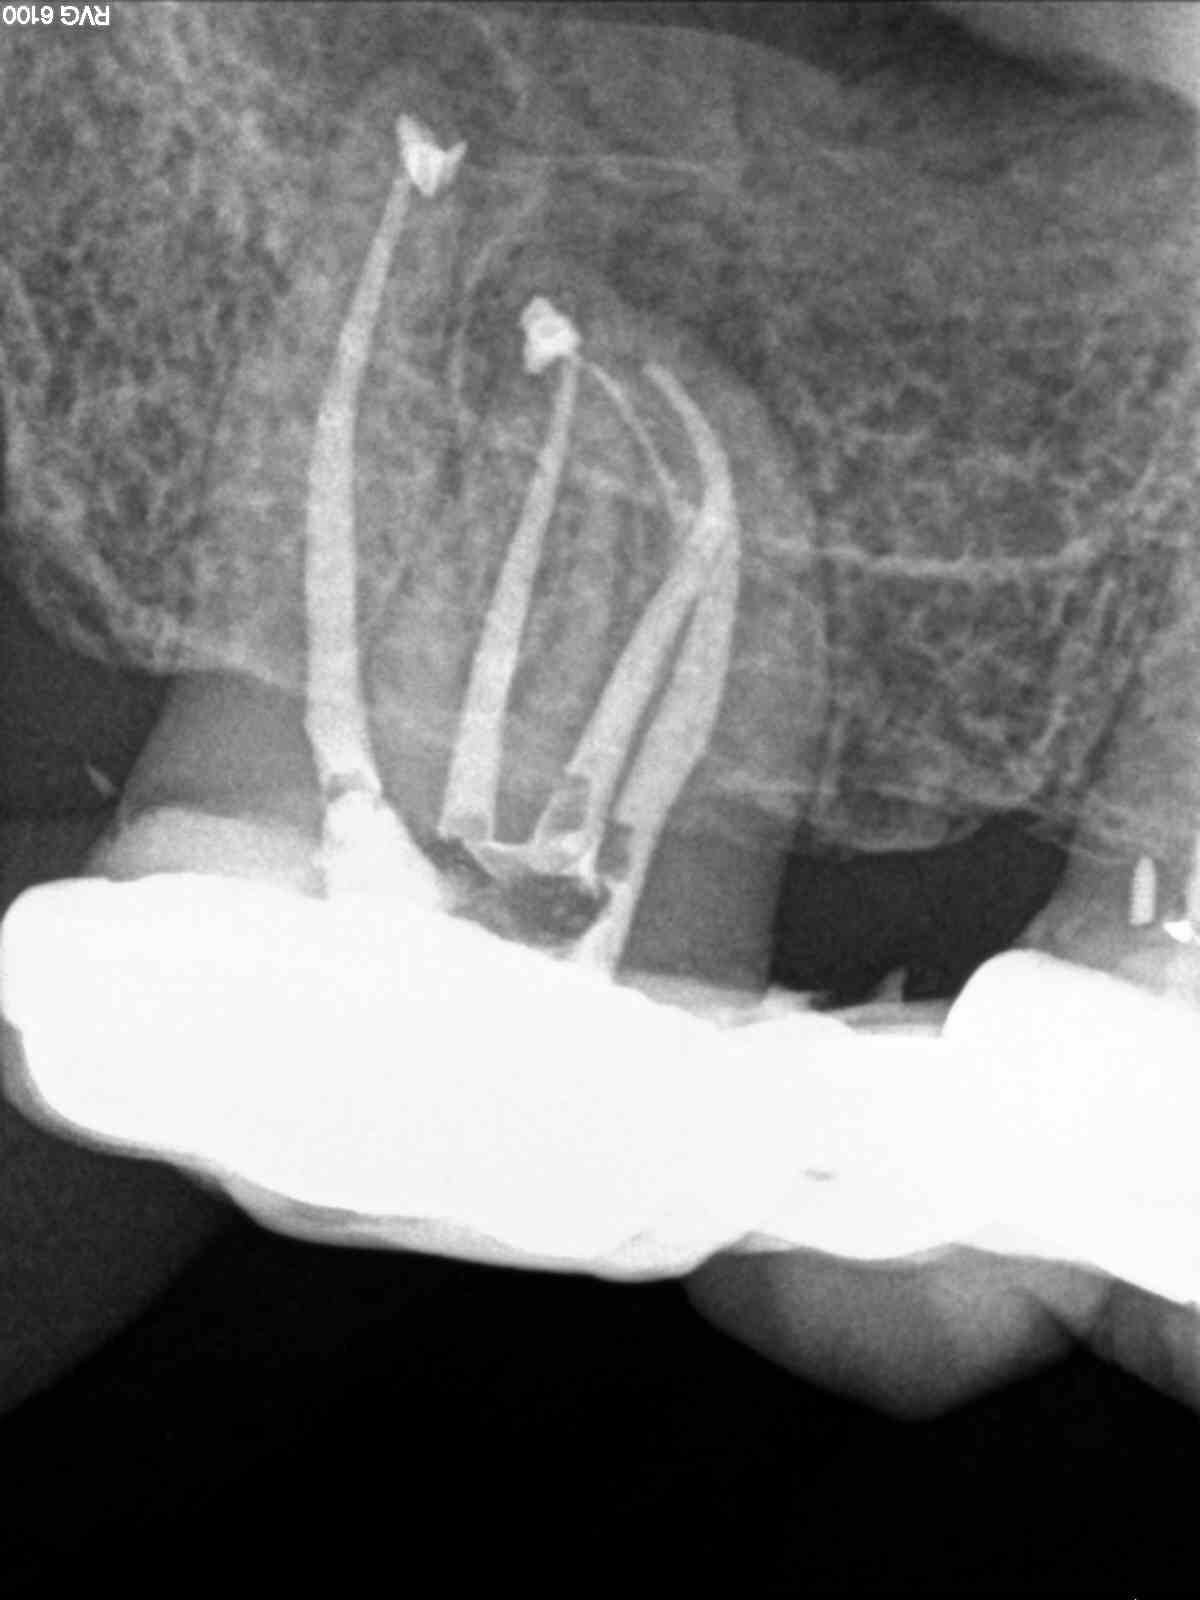

Todos los casos los tratamos igual, con ayuda del microscopio, localizamos los cuatro conductos, instrumentamos con sistema Mtwo, y obturamos con sistema de condensación vertical con ola contínua para hacer el downpack y pistola Obtura II para hacer el backfilling.

Lo que tienen estos tres casos en común, y por lo que decido colocarlos, es por la importancia que tiene la irrigación, por que hay veces que aunque en molares superiores localicemos el conducto Mesio-palatino,  puede que su salida se bifurque y nuestra lima no pueda seguir el conducto por que tiende a seguir recto uniendose al MV.